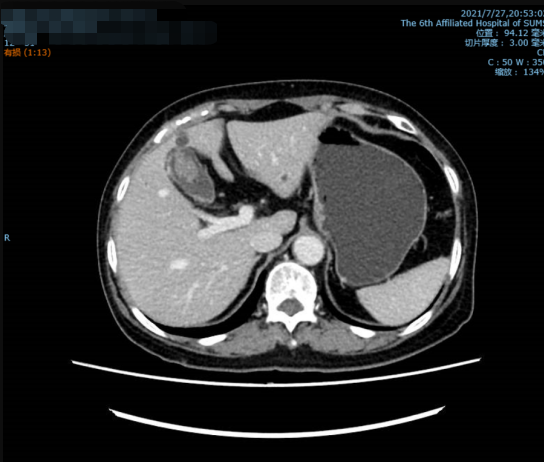

患者住院后,我们给患者复查了肿瘤指标、肝功能指标等,未见异常,增强CT仍提示胆囊癌可能性大,并胆囊多发结石。我们科室讨论后认为根据目前的资料仍无法确定100%就是胆囊癌,但手术需要恶性肿瘤的标准进行。按计划行“腹腔镜胆囊切除+局部肝切除+区域淋巴结清扫”。术后恢复顺利,术后第5天即康复出院。

影像学检查提示息肉较前明显增大,伴胆囊多发结石